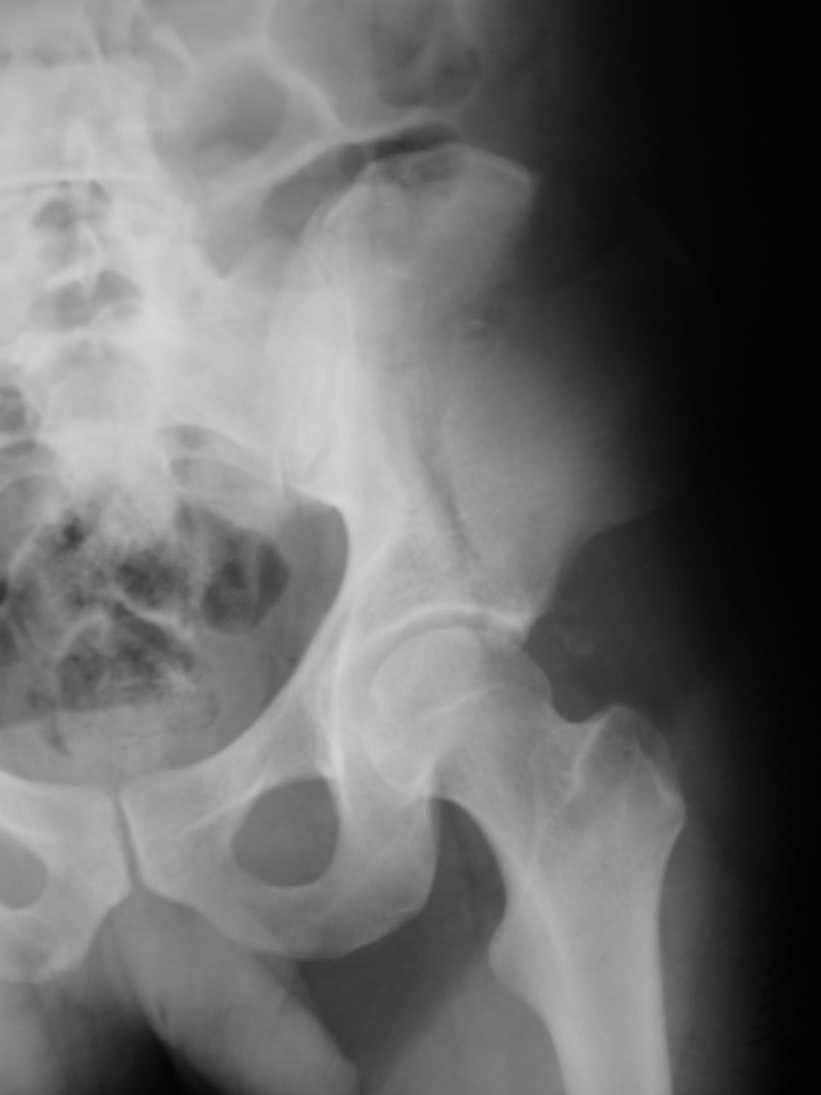

Поступил пациент после кататравмы (упал с высоты 4м). После обследования установлен Ds: Сочетанная травма. ЗТГК перелом 5-6 ребер справа. Ушиб левого леогкого. Оскольчатый перелом крыла подвздошной кости слева, со смещением. в экстренном порядке выполнена операция о/синтез таза стержневым аппаратом. Снимки прилагаются. Пациент со 2-го дня стал ходить без костылей. Из анамнеза жизни у пациента имеется гепатит В и С, с 1998г. употребляет наркотики (героин 1г в день нормальная доза). На контрольных снимках таза в аппарате смещение отломков сохраняется, да еще и стержни сломались. Подскажите ув.коллеги, как поступить в данной ситуации: оставить все как есть или добиваться репозиции в аппарате, или планировать на открытую репозицию. На сегодняшний день пациент стабилен, по анализам компенсирован. Принимает героин по другому справиться не может. С ув. Андрей

А сколько времени прошло после травмы? Аппарат лучше убрать: в таком виде он не выполняет никаких функций, а сломанные стержни скорее всего воспалятся и помешают доступу, если решите оперировать открыто. Целесообразно, как мне кажется сделать проекции Judet, чтоб определиться с линией перелома и возможным вовлечением вертлужной впадины. Вообще же лечение переломов крыла аппаратом - дело достаточно утомительное и часто неблагодарное - сложно управлять ротационным смещением и отведением/приведением фрагментов крыла, можно ухудшить стояние отломков.

Уважаемый Андрей, у пациента имеется перелом передней колонны,и после наложения аппарата положение отломков ухудшилось. возможно не из-за ваших действий а за счет тяги четырехглавой мышцы. Обе ости настойчиво будут тянуть крыло вниз.